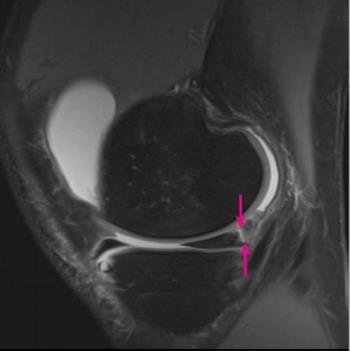

If you have a knee problem, in most situations I believe it will be helpful for you to have such an MRI scan of your knee - to make or support a diagnosis or to exclude other reasons for your problem. MRI scans are particularly useful in the evaluation of meniscus tears, and tears of the anterior cruciate ligament (ACL) and other ligaments. If your main problem is knee pain I believe you should in most circumstances as part of the investigation have an MRI scan of the knee, and indeed I feel you should not have an arthroscopy unless you have had an MRI evaluation. The price has declined considerably over recent years, making MRI a much more affordable aid to diagnosis, and today a knee MRI is close to 400 euros in Denmark (where I practice).